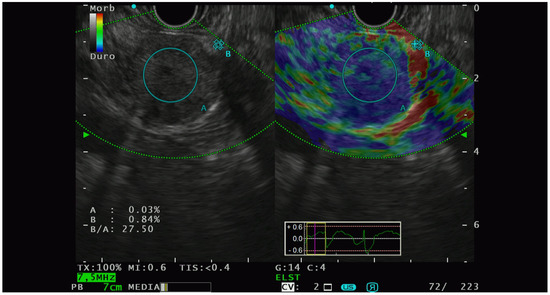

Elastographic characterization has provided different, heterogenous, and sometimes controversial evidence. In 2009, Iglesias-Garcia et al. [41] conducted the first significative prospective analysis on the qualitative elastography pattern of solid pancreatic lesions. They divided the elastography pattern of the lesion of interest in four color regions: from the harder to the softer tissues, they assigned the following colors, respectively: dark blue, green, yellow, and red. All the PNETs diagnosed had a blue pattern at the elastography analysis and all of them were defined as malignant at the pathological analysis. The same group of authors [42] also performed a prospective study with the aim of analyzing the semiquantitative characteristics of PTEN on elastography and they observed that PNET had the highest strain ratio (52.1, CI, 33.96–70.71) among the pancreatic solid lesions including pancreatic adenocarcinoma, chronic pancreatitis, and other inflammatory pancreatic conditions (Figure 2).

Figure 2.

PNET with high lesion-to-parenchyma strain ratio, characterized as G2 with lymphatic invasion at the histological analysis of the surgical specimen.